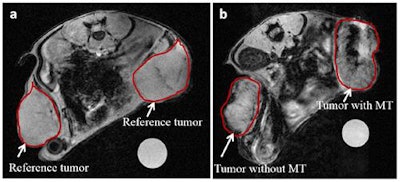

In vivo MR images of tumors before (a) and after (b) injection of ultramagnetic liposomes, with and without magnetic targeting. Image courtesy of C J Thébault et al, Mol. Imaging Biol. 10.1007/s11307-018-1238-3.The researchers created ultramagnetic nanocarriers and applied magnets to target the nanocarriers to colon tumors in mice. They then developed a novel quantification method based on the modification of intensity distributions found in MRI (Molecular Imaging and Biology, 25 June 2018).

With experimental parameters now established, the scientists implanted CT26 murine colon carcinoma cells into the posterior flanks of Balb/C female mice. After two weeks of tumor growth, mice were put under anesthetic and preinjection imaging acquired.

The researchers then placed magnets over the skin of one tumor, leaving the tumor on the opposite flank of each mouse as a control. They intravenously injected ultramagnetic liposomes, then after 30 minutes the magnets were removed, postinjection MR images taken and the animals sacrificed for ex vivo processing.

Ultramagnetic liposomes signal was observed in nonmagnetic targeted tumors due to passive accumulation. To compare the two types of accumulation, the scientists calculated the pixel intensity in each tumor's MRI slices. Intensities were compiled to give a single pixel intensity distribution per tumor, but comparing the mean signals between tumors didn't show any differences.